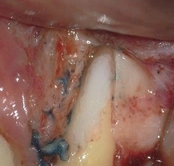

Mid-root crack repair:

Dye used to verify the crack

Crack removed

Filled with GeristoreThe patient was eating and bit down, felt and heard a “pop.” The tooth had cracked in the middle of the root. The tooth helps hold the patients partial in place and did not want to lose the tooth. The crack was removed with the laser and then restored.

The photograph is 2 months after the crack repair. The area looks like nothing was done (no redness, no scarring, etc.) and the tooth is there helping to hold the partial denture.